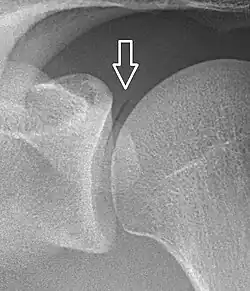

Pneumarthrosis is the presence of air in a joint. Its presentation on radiography is a radiolucent cleft often called a vacuum phenomenon, or vacuum sign.[7] Pneumarthrosis is associated with osteoarthritis and spondylosis.[8]

Pneumarthrosis is a common normal finding in shoulders[7] as well as in sternoclavicular joints.[9] It is believed to be a cause of the sounds of joint cracking.[8] It is also a common normal post-operative finding at least after spinal surgery.[10] Pneumarthrosis is extremely rare in conjunction with fluid or pus in a joint, and its presence can therefore practically exclude infection.[8]

A vacuum sign, or vacuum phenomenon, is a normal finding on shoulder X-rays.